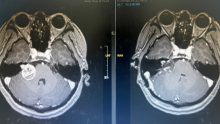

• 大型实性富血运听神经瘤手术复盘

脑肿瘤-神经鞘瘤 其他-自定义

大型实性富血运听神经瘤手术复盘

刘宁

首都医科大学三博脑科医院

昨天18:25 64阅读 0评论 2点赞